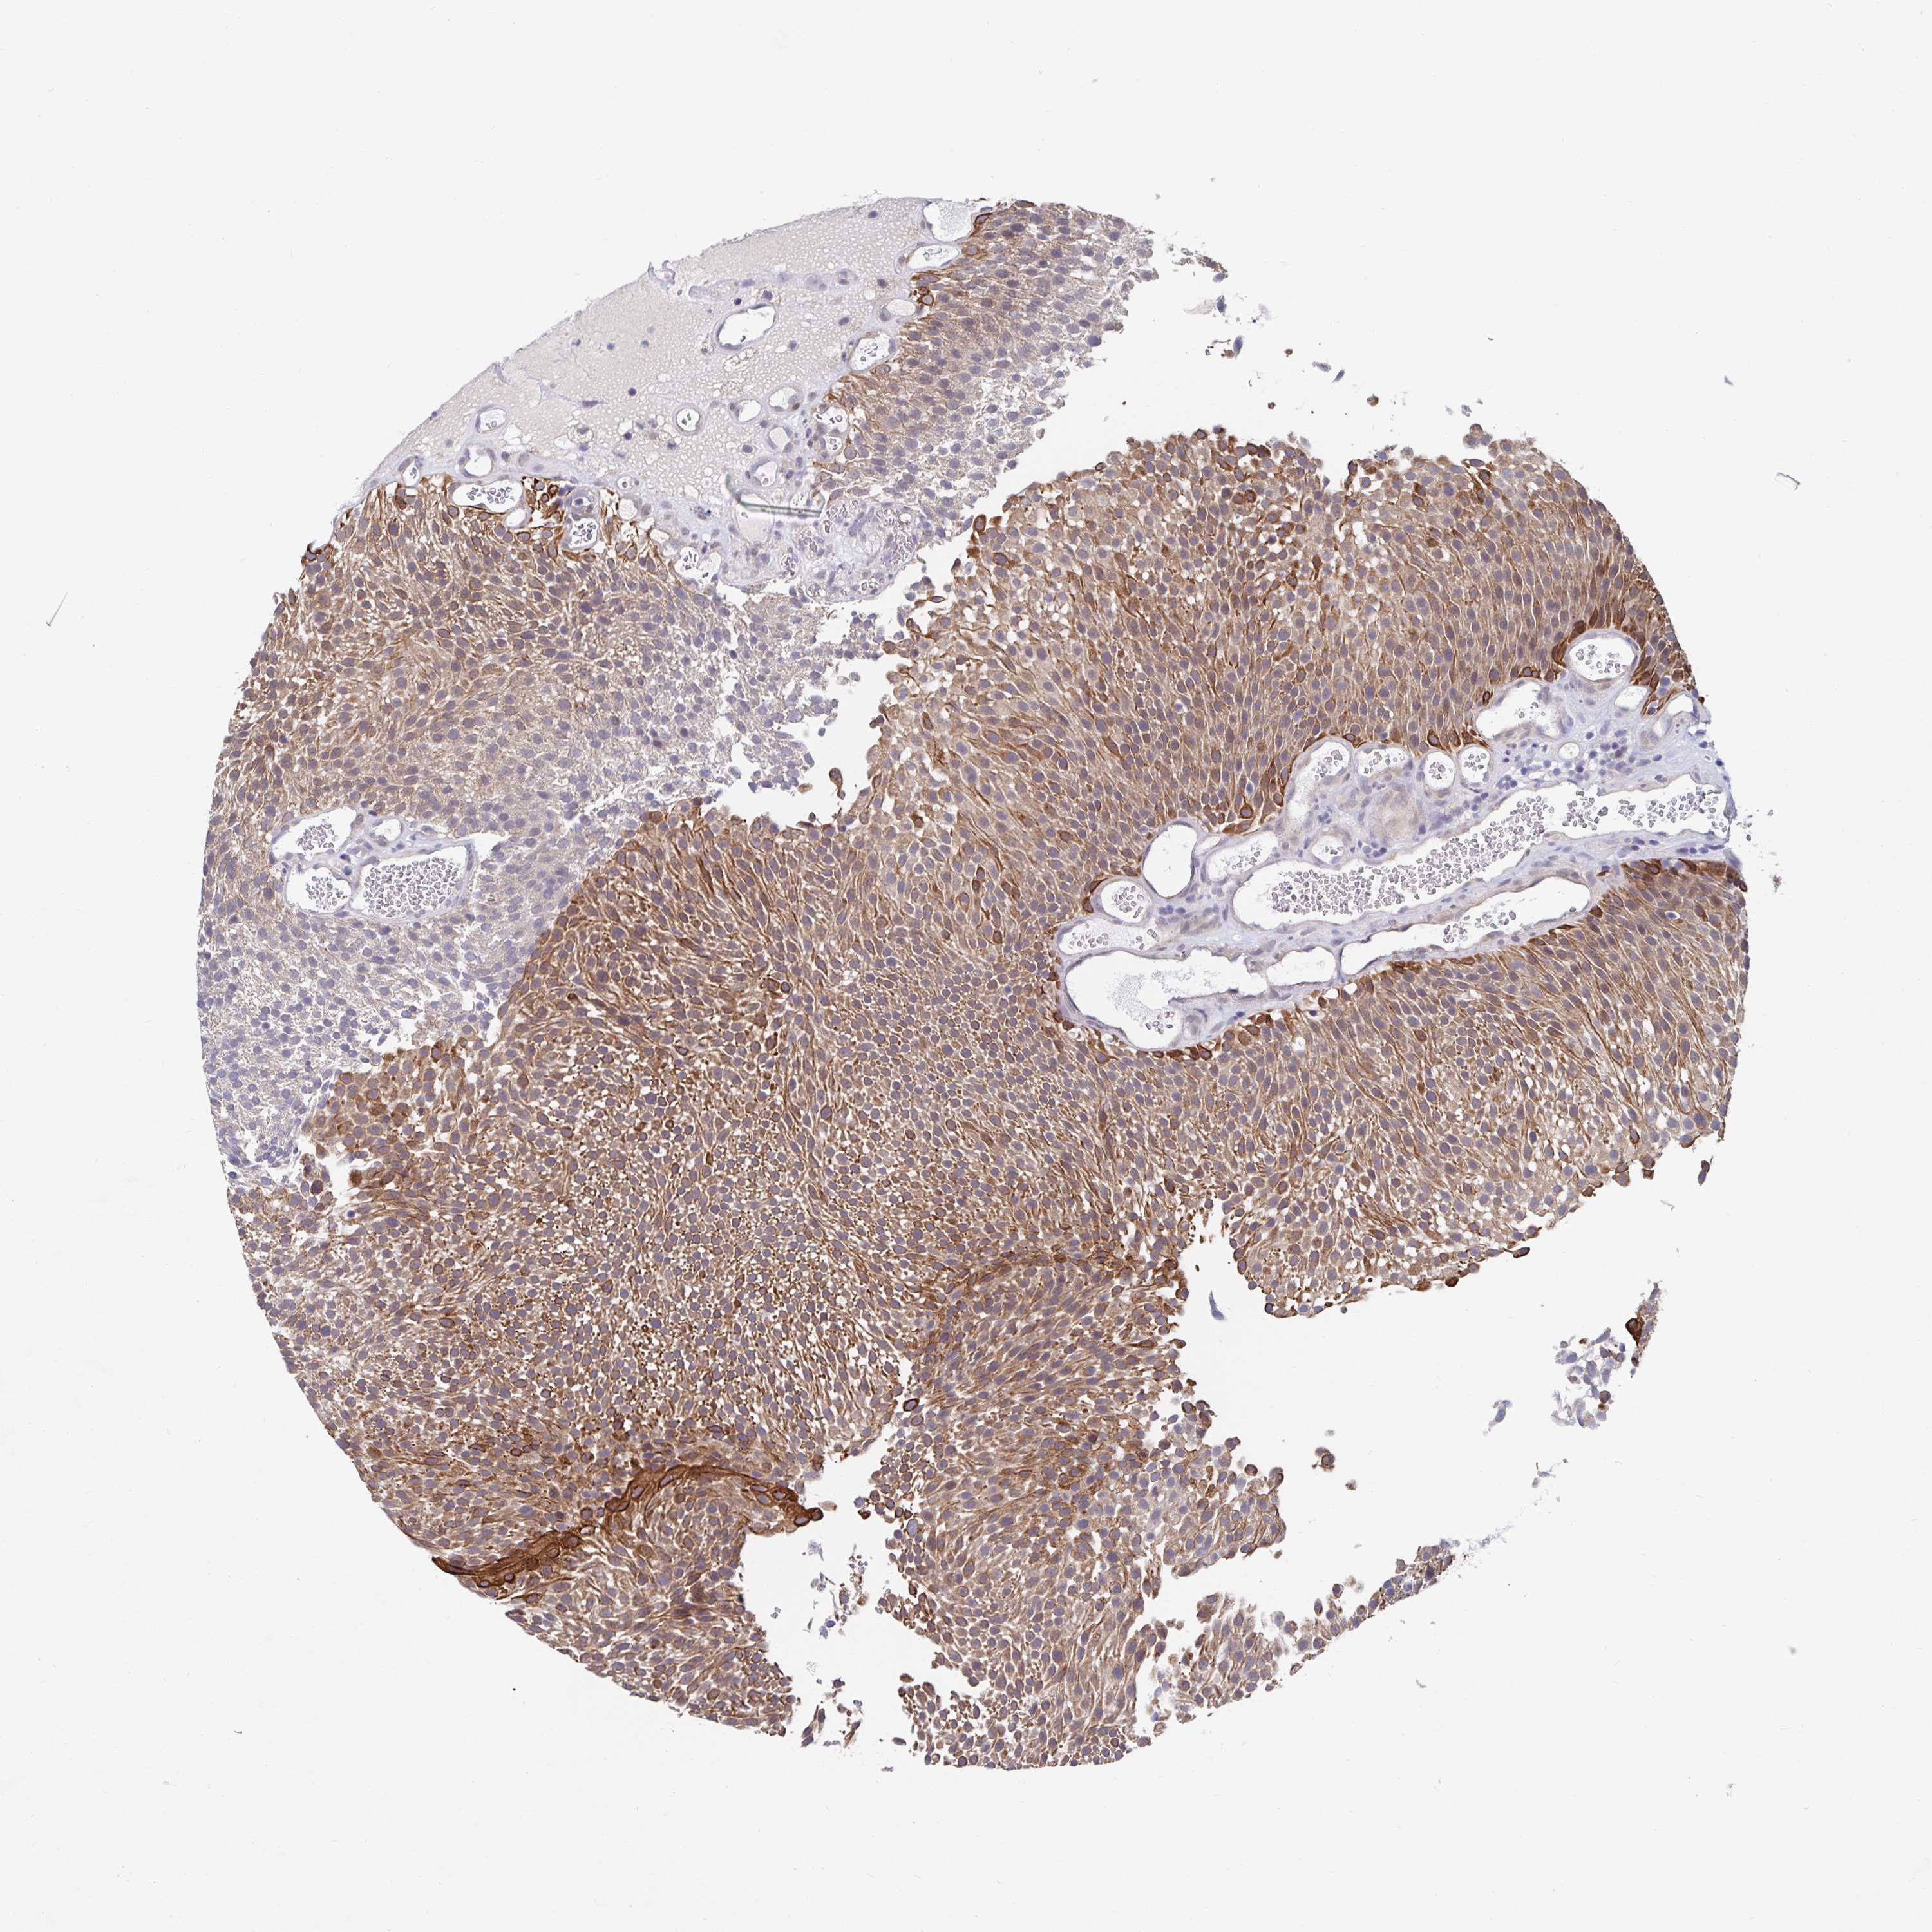

UROTHELIAL CANCER - Protein expressioni

A mouse-over function shows sample information and annotation data. Click on an image to view it in a full screen mode. Samples can be filtered based on level of antibody staining by selecting one or several of the following categories: high, medium, low and not detected. The assay and annotation is described here.

Note that samples used for immunohistochemistry by the Human Protein Atlas do not correspond to samples in the TCGA dataset.

Antibody stainingi

Antibody staining in the annotated cell types in the current human tissue is reported as not detected, low, medium, or high, based on conventional immunohistochemistry profiling in selected tissues. This score is based on the combination of the staining intensity and fraction of stained cells.

Each image is clickable and will lead to virtual microscopy that enables deeper exploration of all samples and also displays staining intensity scores, fraction scores and subcellular localization as well as patient and tissue information for each sample.

Antibody HPA059975

Staining

High

Medium

Low

Not detected

Intensity

Strong

Moderate

Weak

Negative

Quantity

>75%

75%-25%

<25%

None

Location

Nuclear

Cytoplasmic/membranous

Cytoplasmic/membranous,nuclear

Urothelial carcinoma, High grade

Urothelial carcinoma, NOS

Urothelial carcinoma, Low grade